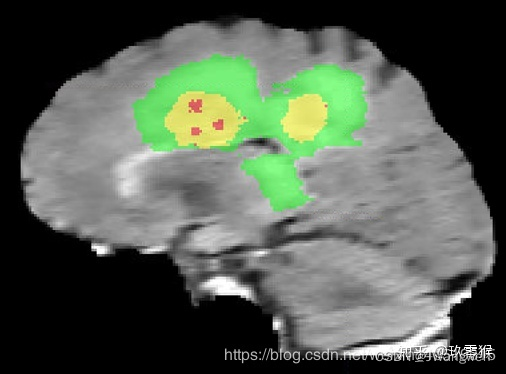

下图是Brats的数据集的一个序列的病例[颜色标签和上面那些图无关],我通过ITK-SNAP导入flair序列以及对应的分割标签, 需要分割有三个部分,分别是WT、ET、TC.

数据集规定, 图中绿色为浮肿区域(ED,peritumoral edema) (标签2)、黄色为增强肿瘤区域(ET,enhancing tumor)(标签4)、红色为坏疽(NET,non-enhancing tumor)(标签1)、背景(标签0)

然后这些标签合并为3个嵌套的子区域:

whole tumor (WT) --------包含所有labels(红+黄+绿)

tumor core (TC) --------- 红色+黄色label

enhancing tumor (ET) -------黄色label

即 WT = ED + ET + NET

TC = ET+NET

ET